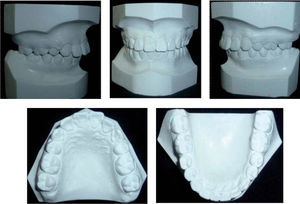

Para la retención se colocó barra fija de canino a canino inferior, además de retenedores circunferenciales superior e inferior (Figura 5).

RESULTADOSComo se observa en las fotografías extraorales, fue posible mantener el perfil y la clase I esquelética, y de esta forma cumplir con los objetivos del plan de tratamiento (Figura 6).

De la misma forma, se realizó la corrección del eje axial de los dientes como se puede observar en la figura 7.

En las fotografías finales intraorales es posible valorar que se obtuvo la corrección de la línea media, la clase I canina bilateral, manteniéndose la clase II molar bilateral; se corrigió el apiñamiento, además de la sobremordida horizontal y vertical.